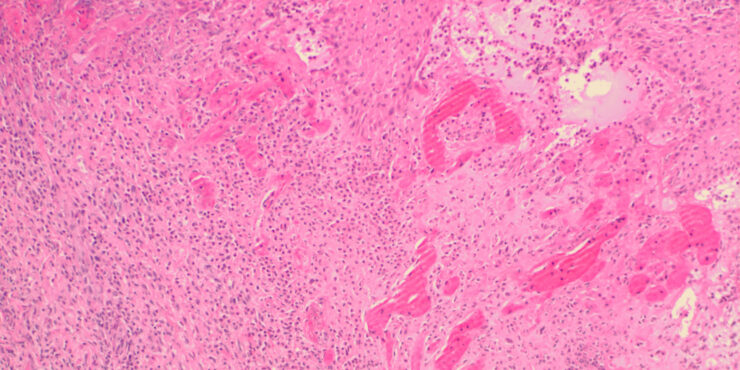

Pseudolymphoma- B-cell Type = اللمفوما الكاذبة بائية الخلايا